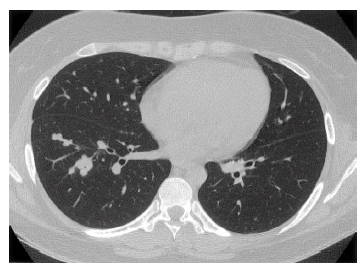

Four months later, chest radiography showed a number of small nodular opacities considered as hematogenous metastasis. Chest CT scan showed variable sized, nodular opacities with vascular connection in the entire lobe of the right lung (Figure 5). Percutaneous transthorasic needle biopsy (PTNB) on the right lower lung nodule was performed, and the pathologic finding was consistent with renal synovial sarcoma (Figure 6). She had received combination chemotherapy with 28-day cycles of ifosfamide 2,500 mg/m2 on day 1 through 3 plus doxorubicin 60 mg/m2 on day 1. After the second cycle of chemotherapy, follow-up chest CT scan showed smaller-sized metastatic nodules on the right lung field, and the state of the response was partial remission. Toxicity was scored according NCl criteria. During chemotherpay, grade 2 neutropenia and grade 1 thrombocytopenia was developed. Non-hematologic toxocities were grade 1 nausea and grade 3 alopecia. Planed doses were administered without dose reduction. After 6 cycles of chemotherapy, complete remission was achieved (Figure 7).

Figure 5.

Chest CT scan shows hematogenous dissemination of variable sized, multiple nodular opacities with vascular connection in the entire lobe of the right lung.

Follow-up chest CT scan shows complete disappearance of multiple nodular opacities after 6 cycles of chemotherapy.